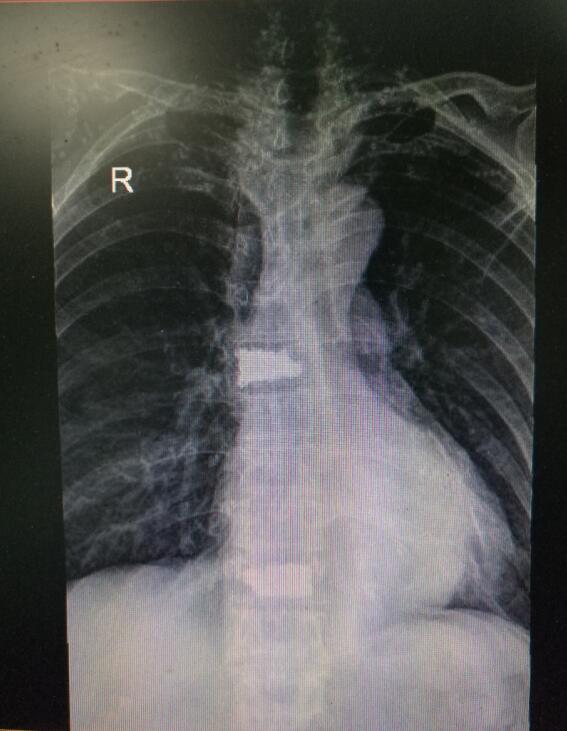

术前DR(数字化的x射线)

入院后第四天,由骨伤二科副主任杨陈一、刘永森医生、唐国皓医生联合为患者成功实施了微创下的经皮穿刺椎体后凸成形术。术后,患者腰背部疼痛逐渐缓解,术后第二天即下床活动。